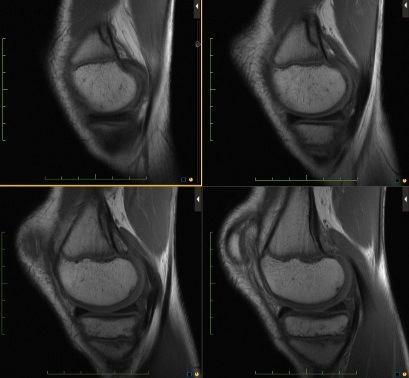

Figure 3 for case Cortical desmoid

Figure 3